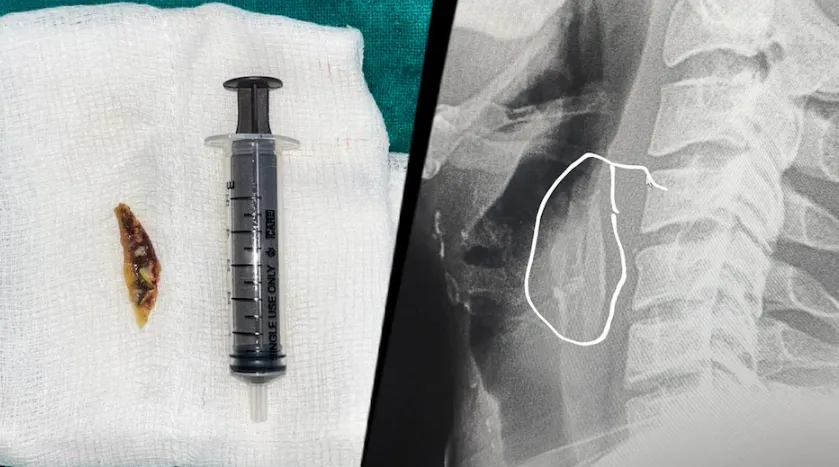

शाजापुर:मामला गंभीर था, और अगर समय पर इलाज नहीं मिलता तो जान भी जा सकती थी। परिजनों ने बिना देर किए युवक को जिला अस्पताल पहुंचाया। यहां डॉक्टरों ने स्थिति को समझते हुए तुरंत सर्जरी का फैसला लिया।

डॉक्टर तेजपाल सिंह जादौन ने बताया कि मरीज को तेज दर्द हो रहा था। सांस लेने में काफी मुश्किल हो रही थी। ऐसे मामलों में अगर देरी हो जाए, तो यह जानलेवा हो सकता है।

इसलिए, समय पर दूरबीन ऑपरेशन करके हड्डी निकालना जरूरी था, जो सफलतापूर्वक किया गया और युवक की जान बचाई गई।